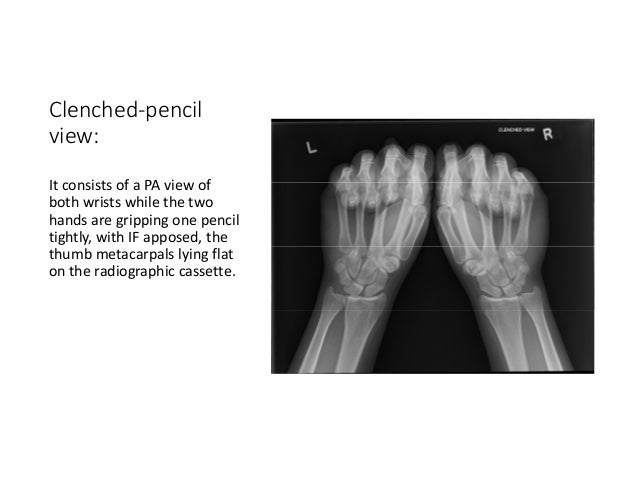

Clenched pencil x ray. 20 3 511 2 lawand a foulkes gd. A pencil to squeeze down on as long as a constant pressure can be maintained. Used to evaluate widening of scapholunate interval.

A modified clenched fist scapholunate stress view. Student uses a pencil for an exam test. Clenching first draws capitate proximally emphasizes any widening of scapho lunate interval.

Pre operative x rays were reviewed including posteroanterior pa neutral and pa ulnar deviation views of the injured wrist and pa clenched fist views of the injured and uninjured wrists. The patient is instructed to grip the pencil with both fists. In scapholunate dislocation discussion.

The clenched fist view is an additional projection used to evaluate suspected widening of the scapholunate interval often performed bilaterally it is a functional view that requires the patient to clench both hands. Male doctor examining x ray image. Thus it is essential to identify this finding on.

Multiple stress x ray imaging positions have been described to assess for sl instability including clenched fist pa and anteroposterior pa clenched pencil pa thumb finger traction and ulnar deviation projections pa and anteroposterior 2 4 6 9 11 13 14 21. 3 patients with dynamic instability of the. The anteroposterior grip carpal stress and posteroanterior clenched pencil radiographic projections are most commonly used to evaluate for dynamic scapholunate instability.

It is the clenched pencil view that is considered the most useful stress view as it allows for comparison with the other wrist. The required materials are a pencil or wooden dowel one 10 12 radiographic cassette and a standard x ray machine. Comparison of radiographic stress.